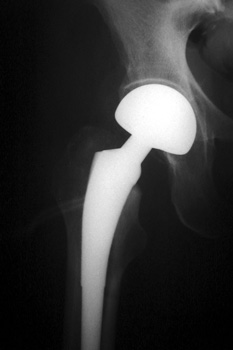

May be associated with pain and loss of range of motion.

HETEROTOPIC BONE FORMATION—Fusing greater trochanter to lateral acetabulum